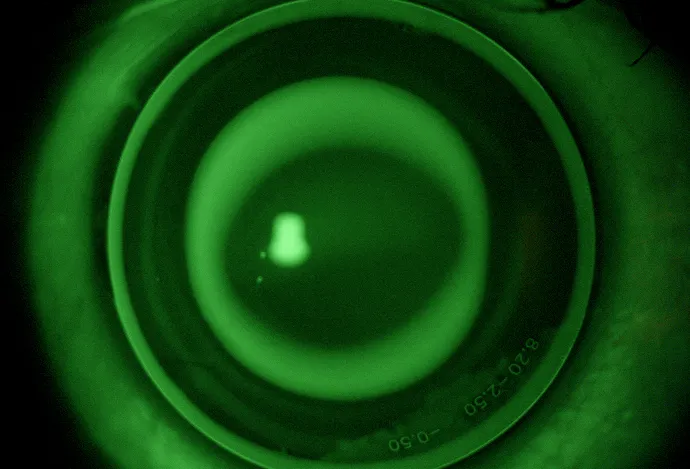

Image: https://www.no7contactlenses.com/medmont-e300/